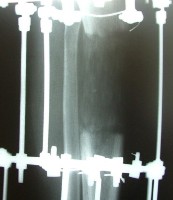

روش تست صحیح انجام کامل کورتیکوتومی: دیستراکشن نباید بیش از 2 میلی باشد، آنگولاسیون نباید بیش از 10تا 15درجه باشد(کج کردن)، روتاسیون نباید بیش از 20تا30 درجه باشد .

ولترال باید محل گپ یکسان با قطر استخوان باشد .APسرعت دیستراکشن:در گرافی از

باریک است سرعت زیاد می شود .f121-اگر استخوان جدید از طرفین برآمده شده و

برآمده شده سرعت کم می شود .f122-اگر استخوان جدید مثل ساعت شنی شده و

3-در بچه ها:5/1میلی متر در روز هم امکانپذیر است،در افراد مسن و در افراد پولیو میلیت:75%یا5/. میلی لیتر در روز

کلا با توجه به گرافی و در نظر گرفتن موارد 1و2تصمیم میگیریم .

درهرکدام کافیست حلقه drop off- بلند کردن تی بیا بیش از 5تا6:دو حلقه با دو وایر در هر کدام و یک وایر

پایین موازی محور آنکل حلقه بالا برای مقابله با فشار عضلات پوستر ولاترال در7والگوس و10درجه فلکشن نسبت به ساق و

حلقه پایین و مصل زانو است.یعنی دو حلقه در قسمت جلو ازهم باز تر و در قسمت مدیال نیز ازهم باز تر هستند .